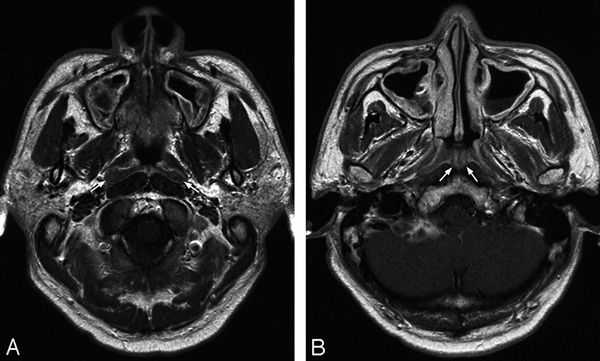

- Аппаратные методы визуализации. В качестве базового исследования применяется рентгенография околоносовых пазух и орбиты. На снимках стенки этих образований могут быть утолщены, а полости затемнены, что является признаками воспалительного процесса и скопления гнойных масс. Также на рентгенограммах видны дефекты стенок, патологические соустья между глазницей и синусами. При недостаточной информативности метода назначаются МРТ, КТ лицевого скелета.